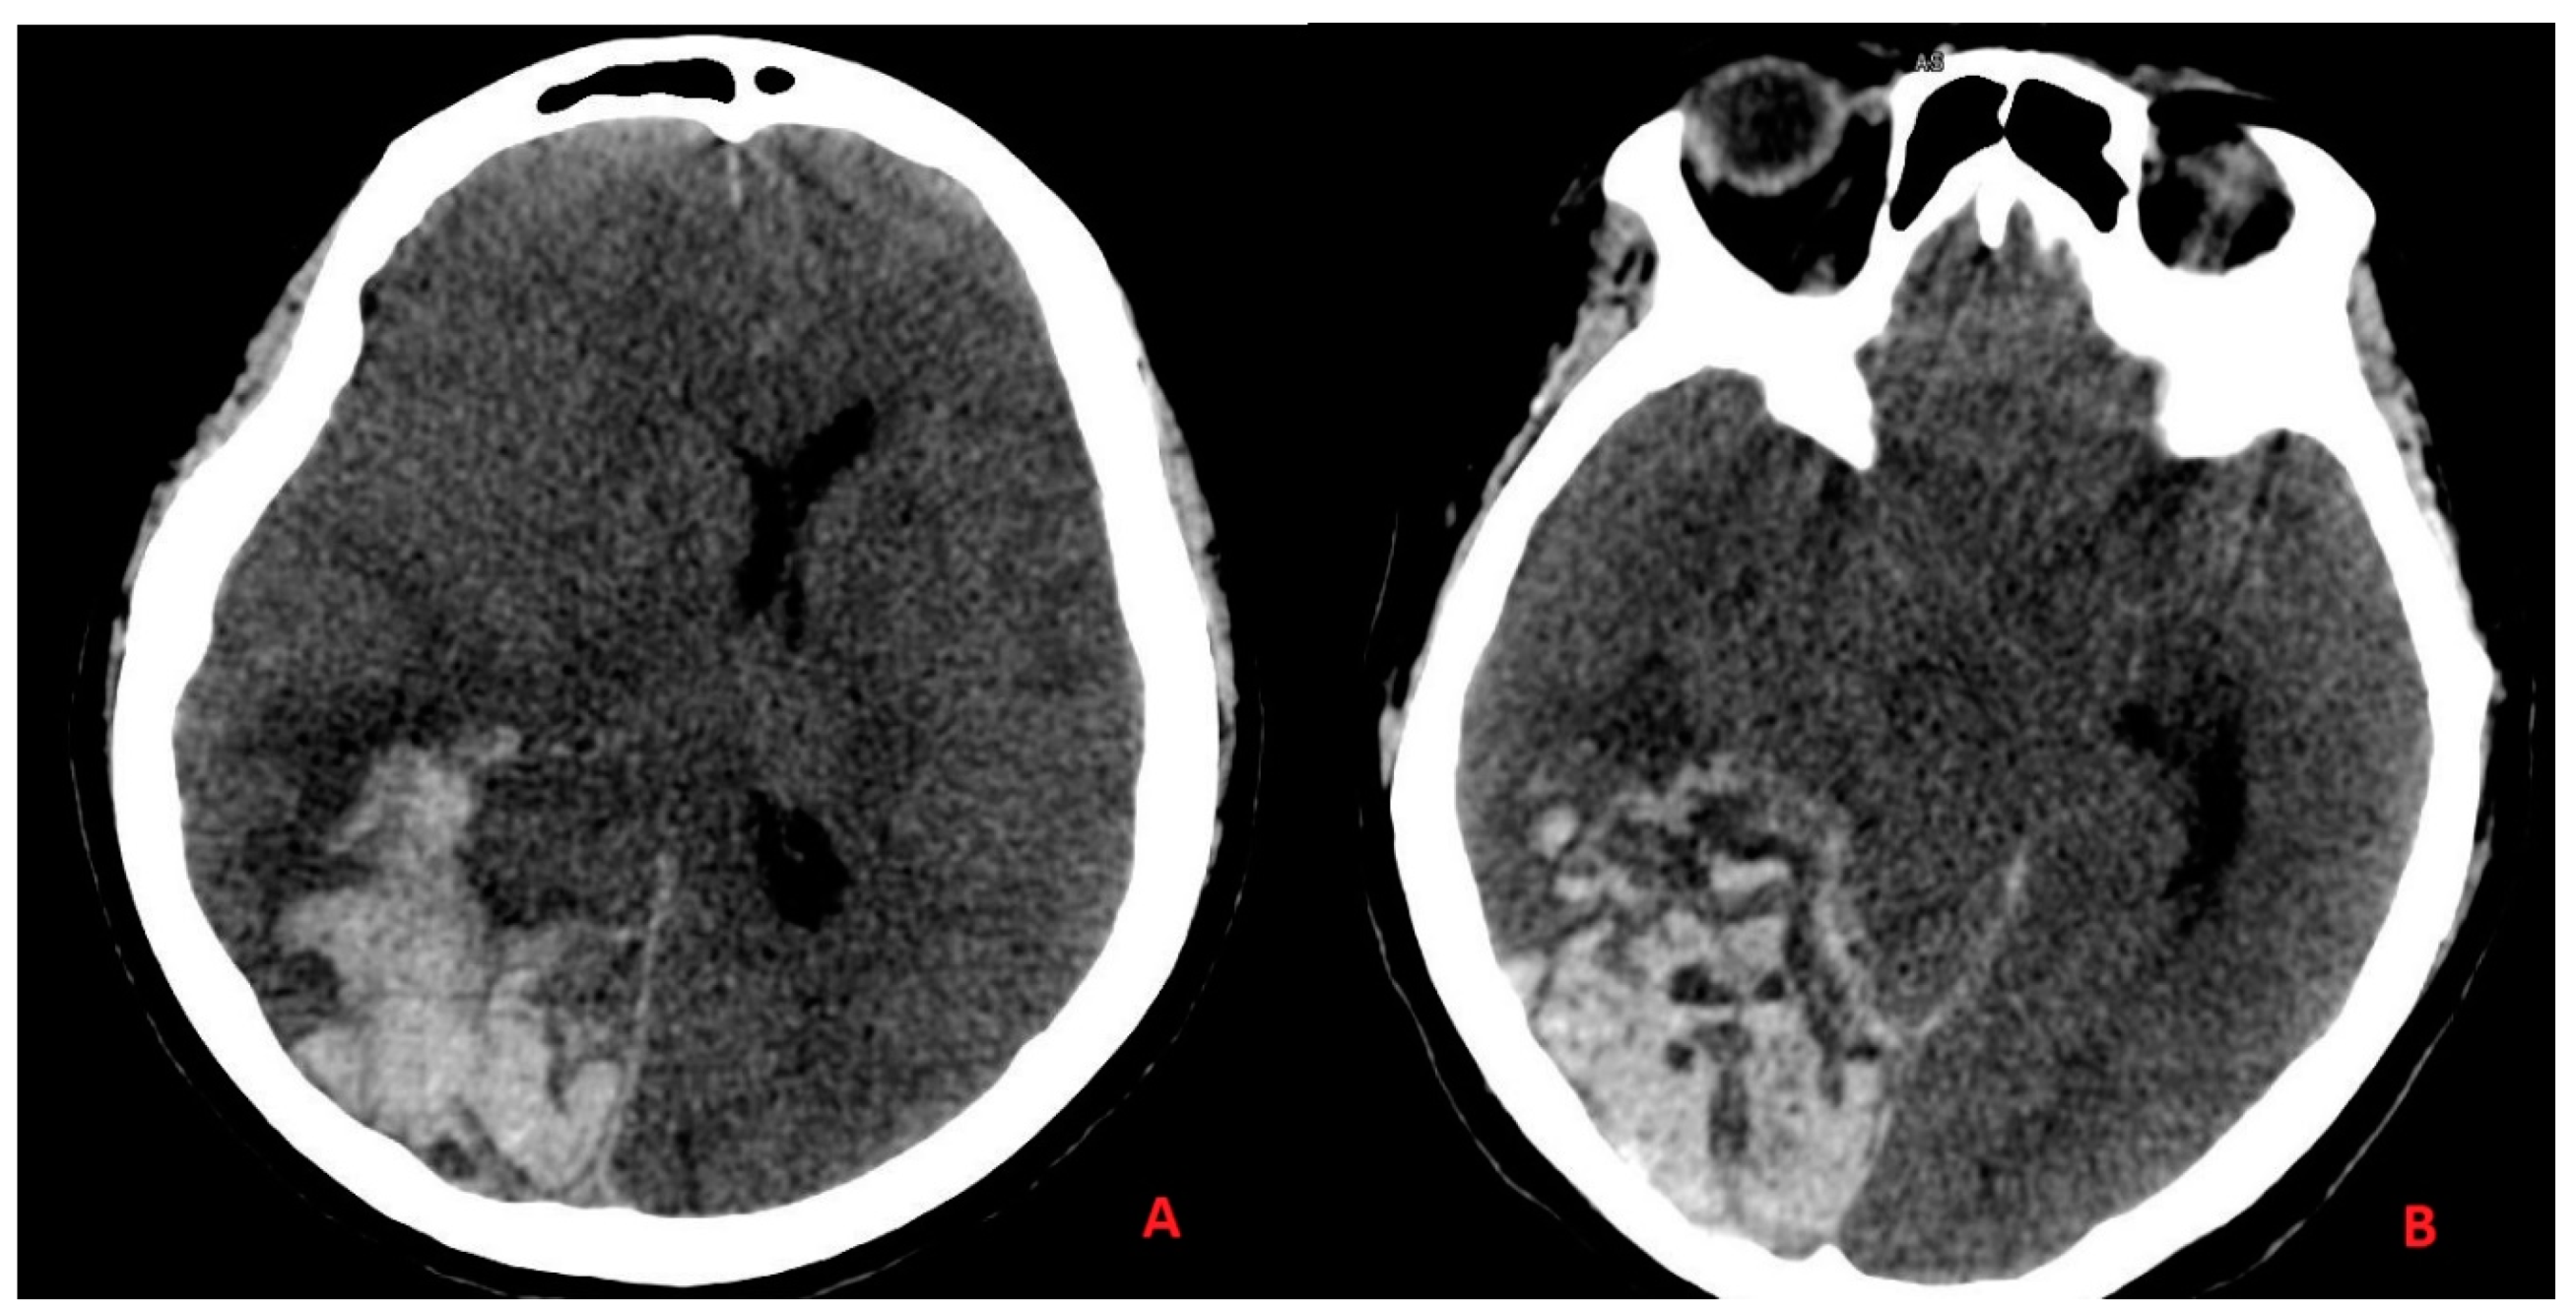

3.2. Case Report 2

3.3. Discussion Part II—Ischemic Stroke and Intracranial Hemorrhage